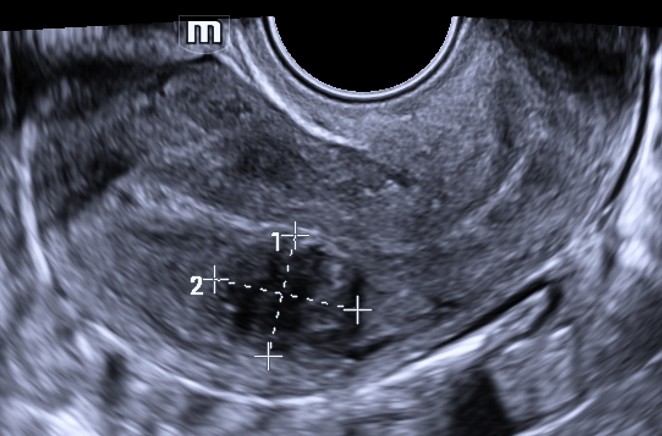

FIGO 2

≥ 50% do mioma é intramiometrial, mas ainda projeta na cavidade.

📋Descrição recomendada para o laudo de US:

Formação nodular miometrial compatível com mioma com 50% ou mais do nódulo localizado dentro do miométrio, apresentando projeção parcial para a cavidade endometrial, produzindo indentação ou assimetria da cavidade.